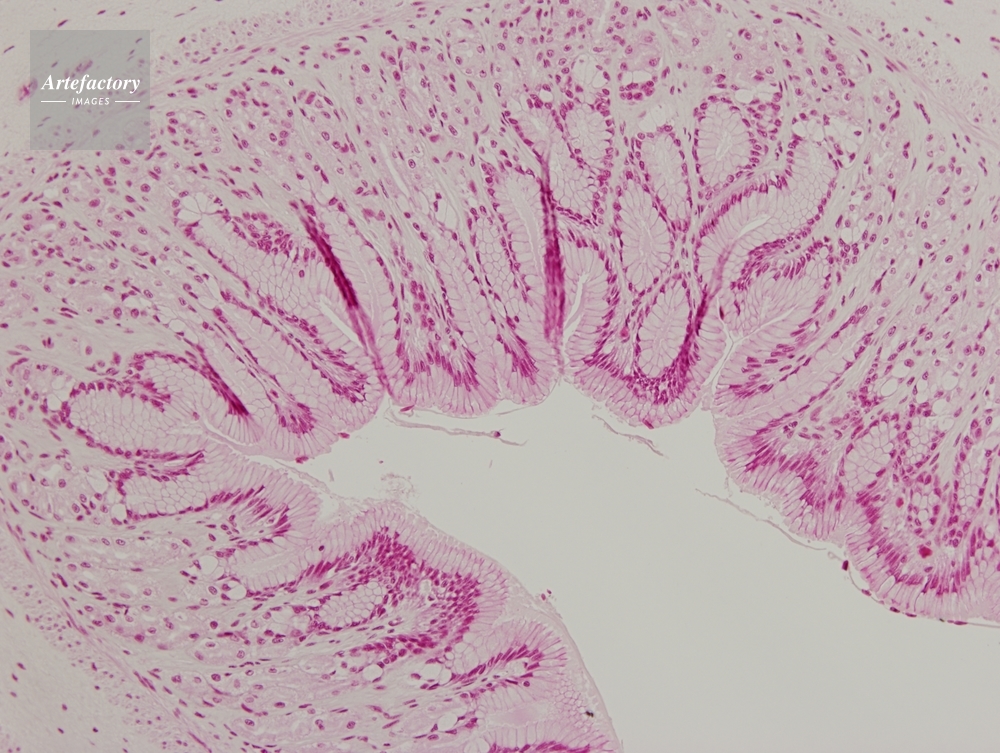

| 作品タイトル | カエル,胃 | モデルリリース | なし | |

| 作家 | OLYMPUS CORPORATION Technolab | プロパティリリース | なし | |